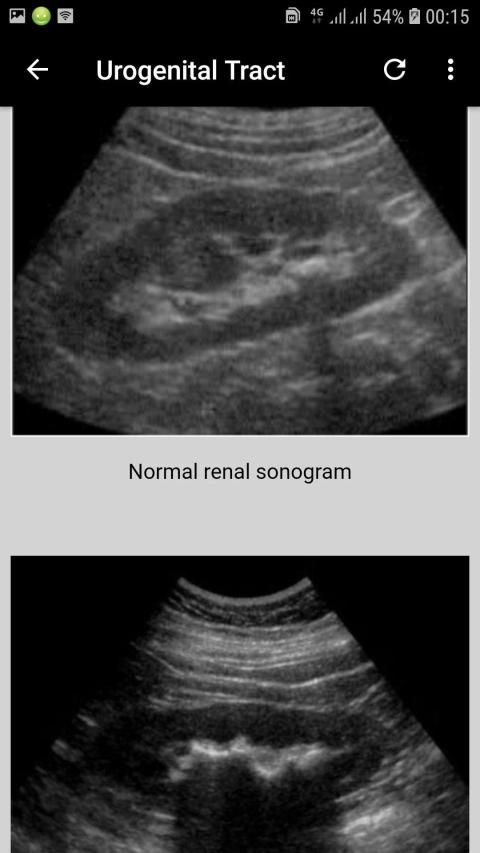

Interpretation of Skull, paranasal sinuses, orbit, chest, abdomen, urogenital tract (pelvis), and musculoskeletal x-rays.

Interpretasi tengkorak, sinus paranasal, orbit, dada, perut, saluran urogenital (pelvis), dan x-ray muskuloskeletal